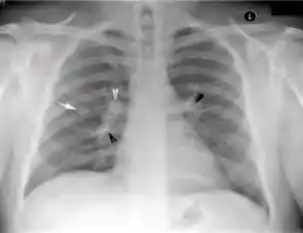

Tuberculosis creates cavities visible in x-rays like this one in the patient's right upper lobe.

In active pulmonary TB, infiltrates or consolidations and/or cavities are often seen in the upper lungs with or without mediastinal or hilar lymphadenopathy.[1] However, lesions may appear anywhere in the lungs. In HIV and other immunosuppressed persons, any abnormality may indicate TB or the chest X-ray may even appear entirely normal.[1]

Old healed tuberculosis usually presents as pulmonary nodules in the hilar area or upper lobes, with or without fibrotic scars and volume loss.[1] Bronchiectasis and pleural scarring may be present.

2. Any cavitary lesion - Lucency (darkened area) within the lung parenchyma, with or without irregular margins that might be surrounded by an area of airspace consolidation or infiltrates, or by nodular or fibrotic (reticular) densities, or both. The walls surrounding the lucent area can be thick or thin. Calcification can exist around a cavity.